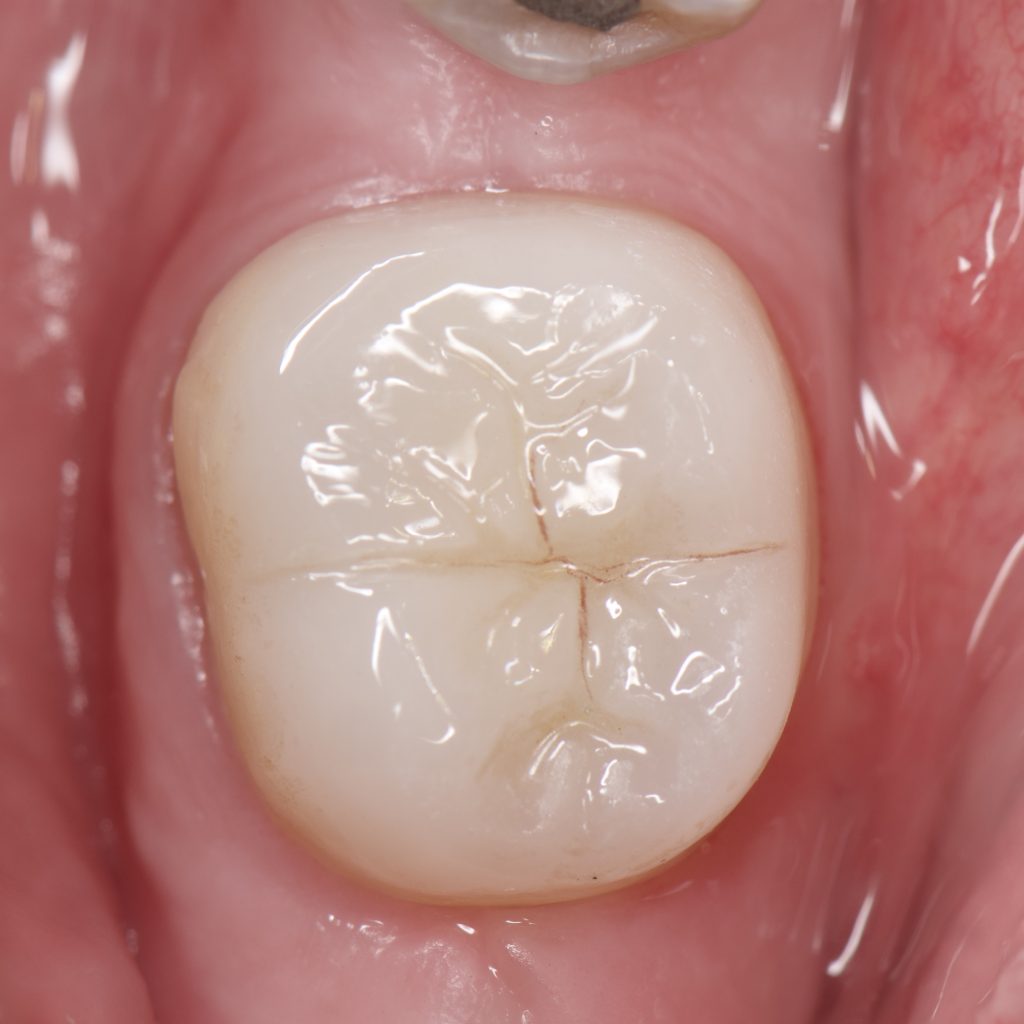

– Sandblasting, Se clearfil Bond , Resin coating, Ever X as dentine replacement And direct composite restoration to complete the biobase

– Circumferential preparation done because the remaining enamel was carious mesially and demineralised buccally and lingually

– E max crown bonded with Heated Ap-x composite